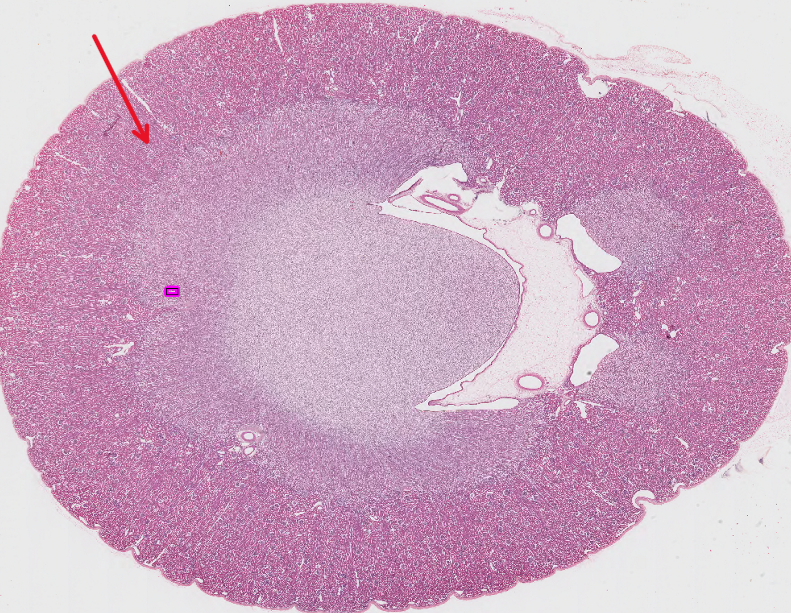

This is a kidney, identify this structure:

Cortex

precortex

medulla